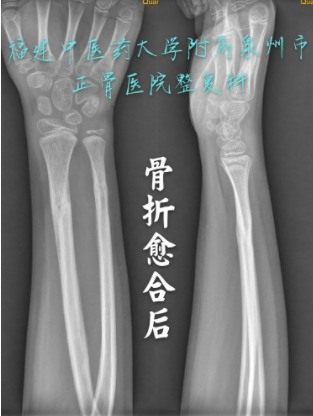

元元X光拍摄照片 — 愈合后(正骨医院供图)

经过小儿骨科和整复科团队一个多月的治疗,元元的手臂恢复良好,手臂变形情况已完全恢复,表面无伤痕,无肿痛症状。通过后续康复训练,元元前臂及腕关节功能恢复良好,与常人无异。元元又变成了以前那个活泼好动、阳光自信的小男孩。